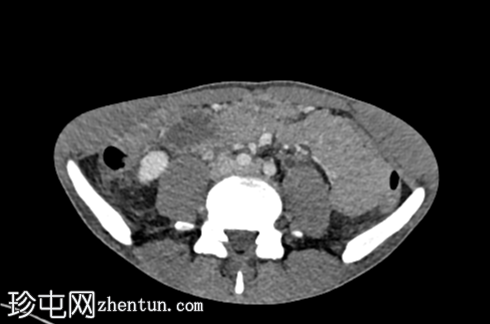

轴位增强CT(门静脉期)

增强CT扫描显示双侧肾积水、输尿管积水伴输尿管黏膜弥漫性强化,以及膀胱容量缩小伴黏膜强化。未见尿路结石或肾周脂肪浸润/积聚。

考虑到患者有氯胺酮滥用史,CT扫描结果符合氯胺酮诱发性尿路病变的诊断。